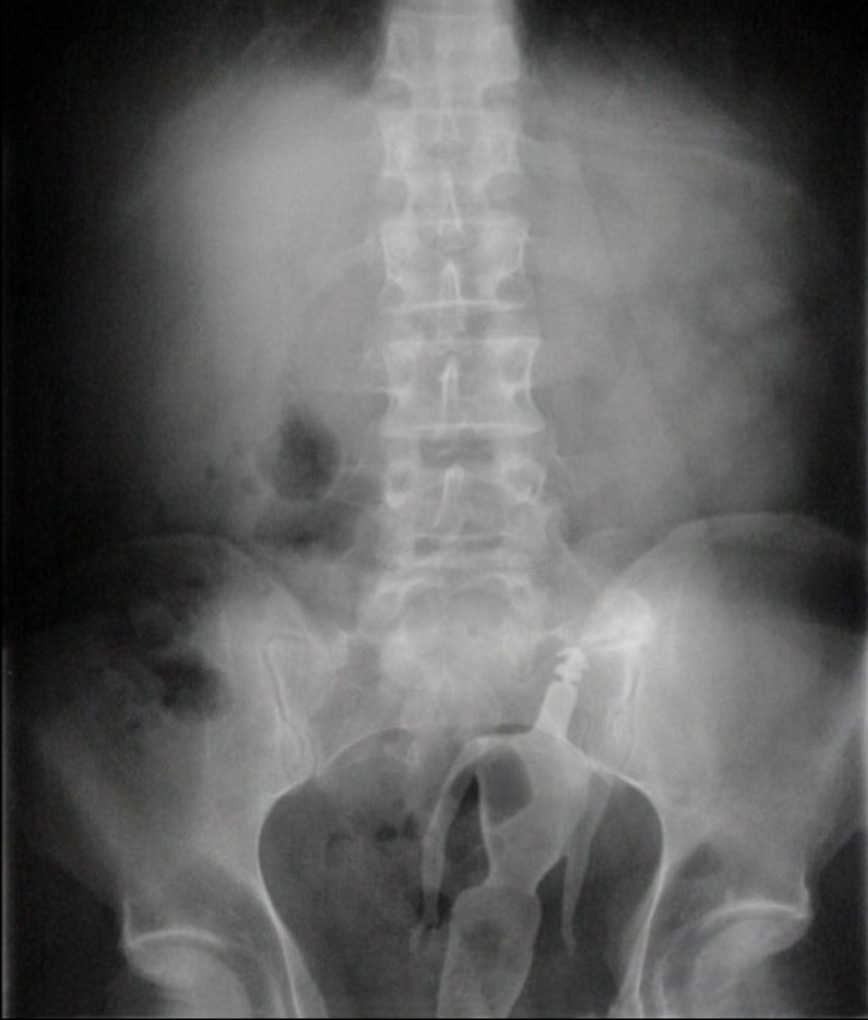

5. Une aiguille à crocheter

« Un collège a eu un patient qui s’est entré un crochet dans son pénis alors qu’il était saoul. L’urologue sur appel a dû l’opérer pour le lui retirer. »